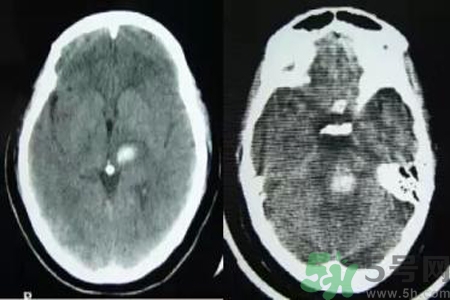

腦出血也稱腦溢血。顧名思義,腦出血是指腦實(shí)質(zhì)內(nèi)的血管破裂,血液溢出即為腦出血。那么腦出血的發(fā)病因素是什么?腦出血的并發(fā)癥有哪些?